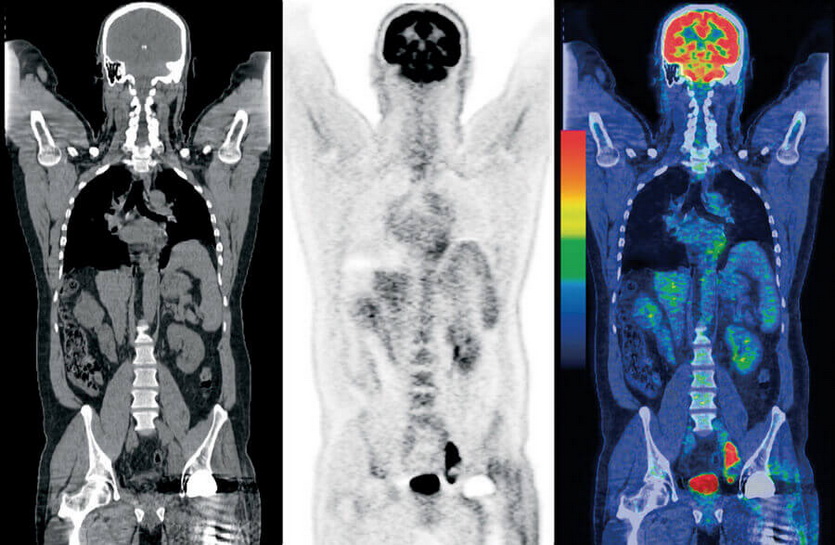

Полная томография позволяет находить рак на ранних стадиях